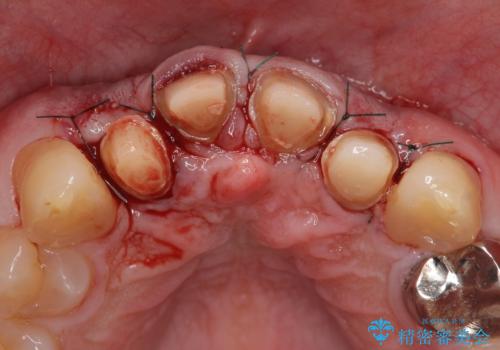

- 前歯の見た目が気になるといらっしゃった方の症例です。

再根管治療後、オールセラミッククラウンによる補綴を行いました。

右上2は歯茎のラインを整えるため歯周外科を行っております。